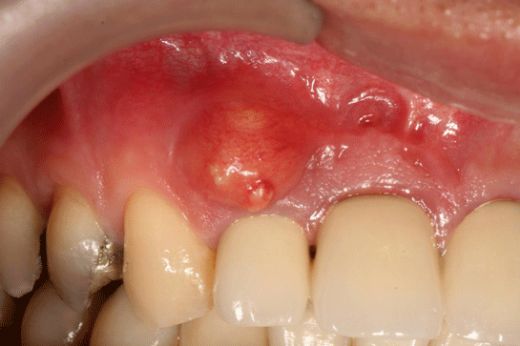

Dişim de çürük olmamasına rağmen diş üstünde ki damakta et şişme yaptı. Hem ağrı yapıyor hem şişkinlik rahatsızlık veriyor bu durumun diş ile ilgisi var mı ve

Safiye hanım, bu tür bir şişlik ve ağrı, diş kökü enfeksiyonu veya periodontal hastalık gibi dişle ilgili bir sorunun işareti olabilir. Kesin bir teşhis ve uygun tedavi için bir diş hekimine başvurmanızı tavsiye ederim. Geçmiş olsun.